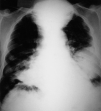

Fig. 1.

Fig. 2.

Fig. 3.

Fig. 4.